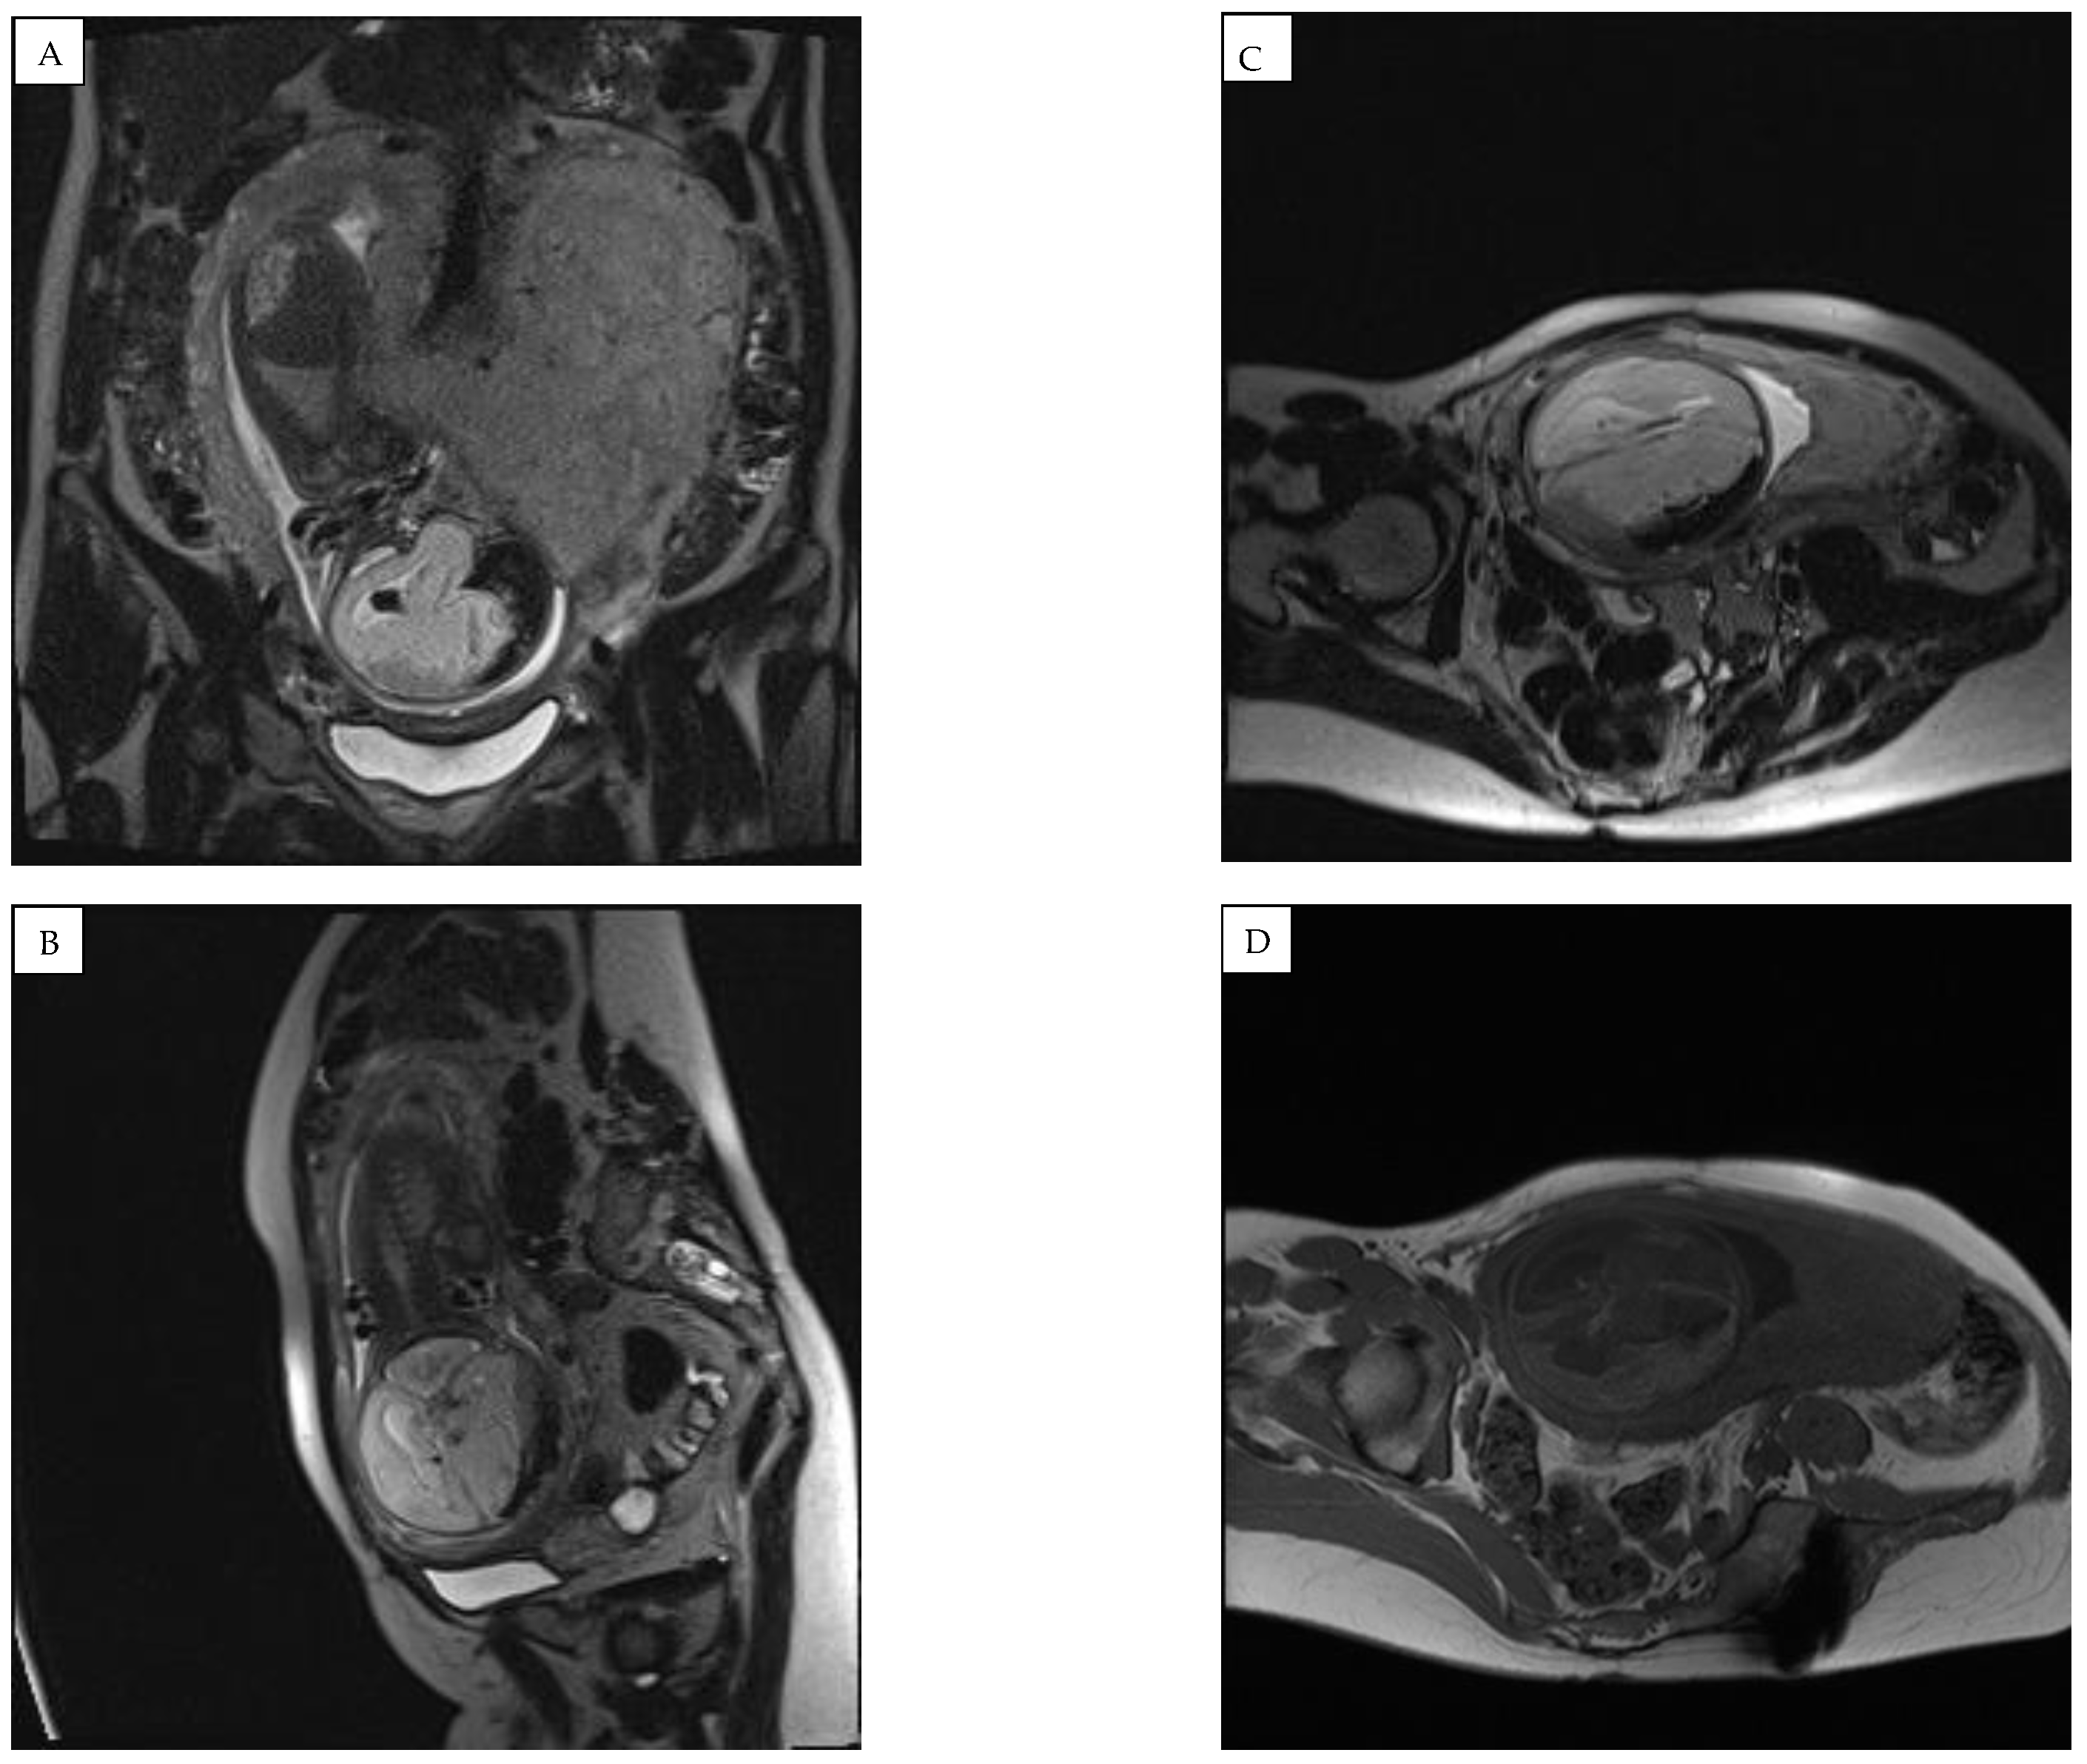

Figure 4.

Magnetic resonance imaging (MRI) of the fetal brain was conducted to confirm the diagnosis of expansion of the right subdural space. (A) coronal plane and (B–D) saggital plane magnetic resonance images showing a hemorrhage with compression of the right hemisphere and a shift to the left of the midline structures was found, along with an accumulation of hemorrhagic signals in the right parasellar part.